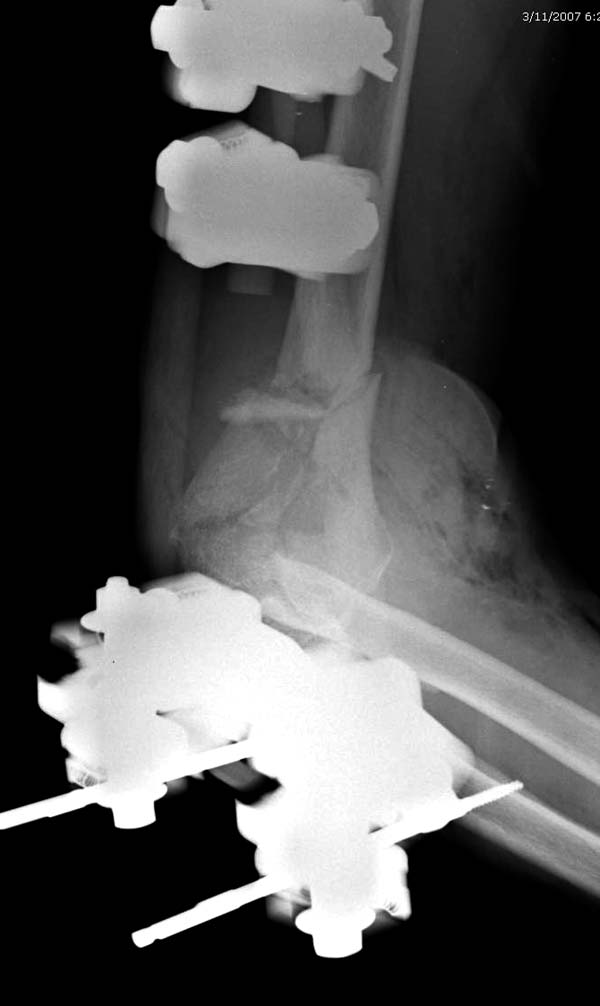

Здесь открытый перелом, временный наружный фиксатор и окончательная фиксация пластинами. Второй случай фиксация без остеотомии отростка пластинами Biomet-DePuy...